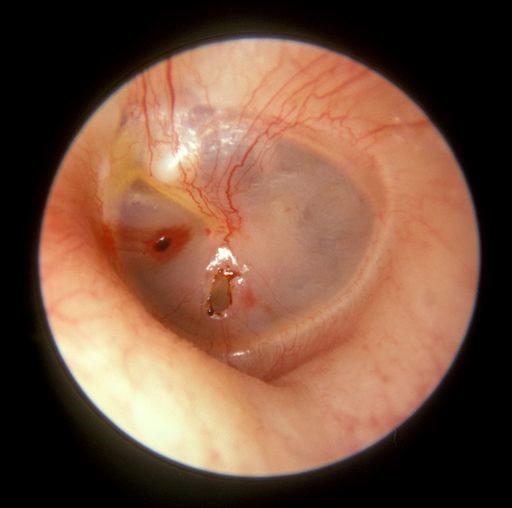

Perforation of the tympanic membrane

By Michael Hawke MD (Won work), CC BY 4.0, via Wikimedia Commons

Chronic suppurative otitis media (CSOM) is a chronic inflammation of the middle ear and mastoid cavity. It is predominantly a disease of the developing world. Clinical features are recurrent otorrhoea through a tympanic perforation, with conductive hearing loss of varying severity.

The tympanic membrane is perforated in CSOM. If this is a tubotympanic perforation (in the centre of the tympanic membrane), it is usually 'safe', whilst atticoantral perforation (at the top of the tympanic membrane) is often 'unsafe'. Safe or unsafe depends on the presence of cholesteatoma: